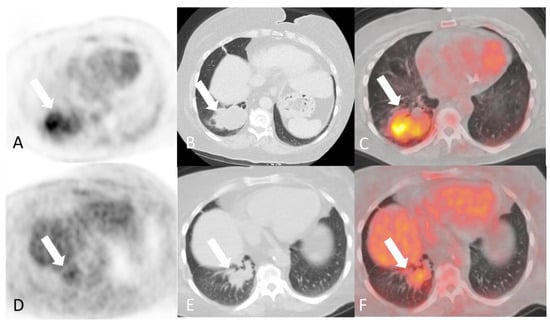

- Soussan, M.; Abisror, N.; Abad, S.; Nunes, H.; Terrier, B.; Pop, G.; Eder, V.; Valeyre, D.; Sberro-Soussan, R.; Guillevin, L.; et al. FDG-PET/CT in patients with ANCA-associated vasculitis: Case-series and literature review. Autoimmun. Rev. 2014, 13, 125–131. [Google Scholar] [CrossRef]

- Kemna, M.J.; Vandergheynst, F.; Voo, S.; Blocklet, D.; Nguyen, T.; Timmermans, S.; van Paassen, P.; Cogan, E.; van Kroonenburgh, M.; Tervaert, J.W.C. Positron emission tomography scanning in anti-neutrophil cytoplasmic antibodies-associated vasculitis. Medicine 2015, 94, e747. [Google Scholar] [CrossRef] [PubMed]